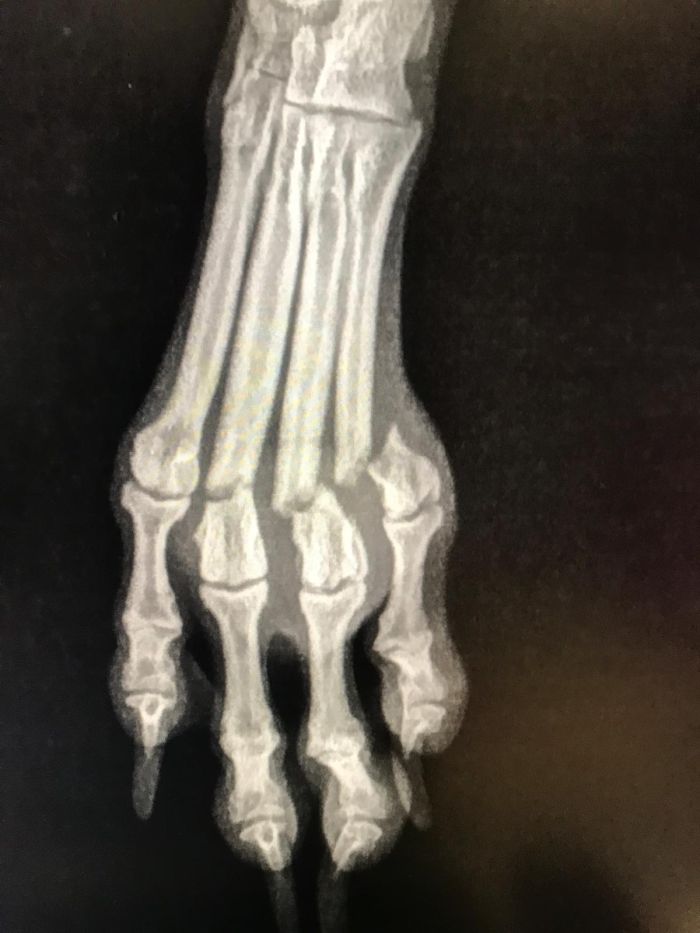

Fixation durch Markraumnägel / Pins

Zusätzlich zur Plattenosteosynthese werden öfters sogenannte Pins oder Markraumnägel verwendet, um einen Bruch in der Längsachse zu stellen.